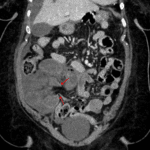

- Displaced loop of small bowel in the right lower quadrant with mild distension (measuring up to 3.5 cm in diameter) and mural thickening and hypoenhancement

- Two transition points are noted involving the afferent and efferent bowel segments, which are in close proximity to each other

- Small to moderate volume free intraperitoneal fluid, including right lower quadrant interloop fluid, without loculated collection or free air

- Closed-loop small bowel obstruction

Findings concerning for closed-loop small bowel obstruction in the right lower quadrant, likely related to an internal hernia in the setting of prior Roux-en-Y gastric bypass. No pneumatosis, portal venous gas, or pneumoperitoneum.